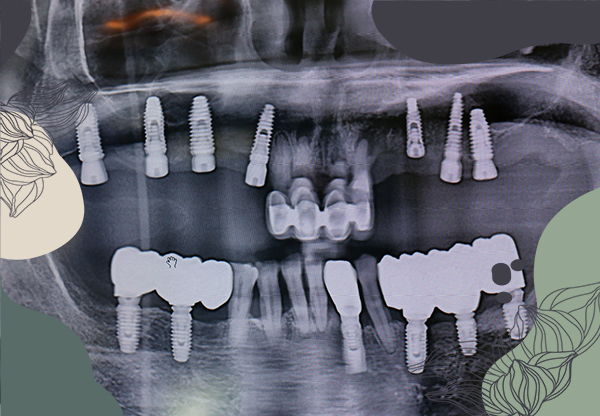

在植牙前,植牙醫師需要為患者進行仔細評估,

目的就是降低植牙可能的風險。

醫師會透過諮詢、檢查與電腦掃描等方式來確認患者目前的身體狀況,

而患者也應該將自身狀況如實回報給醫師,

才能讓醫師更好的設計患者專屬治療計畫,並降低風險。